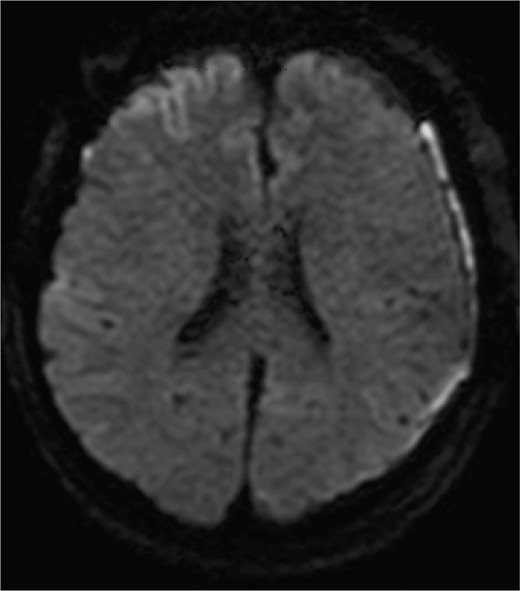

A man in his fifties presented with sudden severe headache that showed no improvement. Initial CT at another hospital revealed SDH, prompting referral to our institution. Head CT demonstrated left SDH including the interhemispheric fissure (Fig. 1). 3D-CTA performed at the referring hospital revealed ⁓5-mm saccular aneurysms at the left ICA and right basilar-superior cerebellar artery junctions, along with left A3-A4, and right A2-A3 aneurysms (Fig. 2). Preoperative FLAIR imaging showed no evidence of SAH (Fig. 3). As the initial 3D-CTA inadequately captured the distal portions of the ACA, we performed repeat imaging upon admission, which revealed an additional left A3A4 DACA aneurysm. However, due to the DACA aneurysm being smaller than the ICA aneurysm, definitive determination of the rupture source was not possible.

Diffusion-weighted images on postoperative day 3 are shown. No obvious ischemic changes are seen.

Given the uncertainty regarding the rupture site, we first performed left frontotemporal craniotomy, which confirmed an unruptured ICA aneurysm. Subsequently, bilateral frontal craniotomy was performed with careful evacuation of the SDH. The callosomarginal artery was readily identified in a relatively shallow subarachnoid space during interhemispheric fissure dissection. No SAH was observed. The aneurysm body demonstrated strong adhesion to the left side of the falx cerebri, with white thrombus continuous with the SDH, identifying it as the rupture site. Both the left ICA and DACA aneurysms were successfully clipped. Postoperative diffusion-weighted imaging on day 3 showed no frontal cortical ischemic changes (Fig. 3). DACA flow without vasospasms was confirmed by cerebral angiography on day 8. The patient was discharged without neurological deficits.